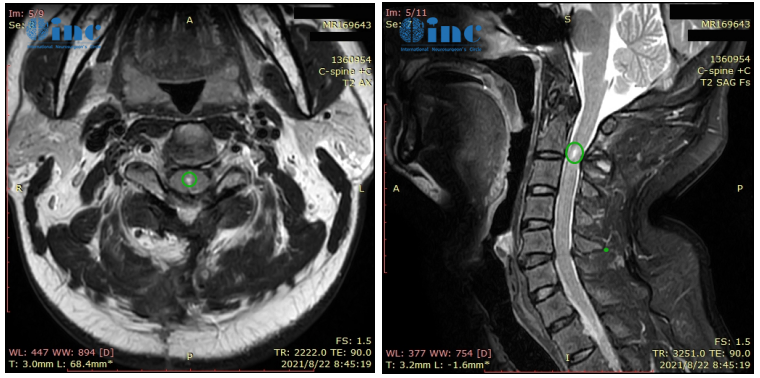

术后3个月回访:

“8月22日的核磁共振成像看起来很棒,令人满意!肿瘤被很好地切除了。磁共振成像上只有一个很小的切除腔。此外,病理学方面,我们预估的室管膜瘤II级得到证实。我建议患者未来每年进行一次MRI检查……”这是INC国际神经外科顾问团的德国Helmut Bertalanffy(巴特朗菲)教授对刘先生术后3个月的随访回复。